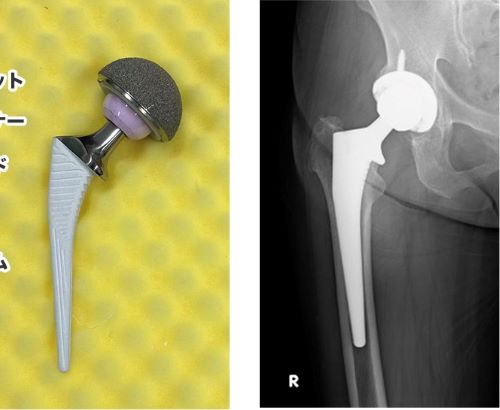

「知らなくて良い事!!」2024.11.24以前「継続は力、努力は裏切らない!!」変形性股関節症治療の為に人工股関節置換術を受けた。と言うブログを書きました。軟膏が擦り減った股関節に骨を削って人工関節を埋め込む手術です。先日、術後3ヶ月の検診を受けました。「順調ですね。問題ありません。」ドクターのディスプレーには添付の如く人工関節のレントゲン写真画像が写っていました。びっくりしました。私は擦り減った軟骨の代わりにチタンの薄いプレートの人工関節が入っていると思っていたからです。本当に人工の股関節が入っていたとは思っていませんでした。事前に「手術に4時間掛かる。」とドクターから聞かされていて、薄いプレートを入れるために骨盤と大腿骨を削るのに長時間かかるのだなと少し疑問に思っていました。大腿骨を切り取って写真の様な人工関節を埋め込み骨盤とボルトで留める手術あれば逆に4時間でも短く感じます。本当に人工の股関節を置換する手術でした。昨年の年末に親戚の小児科医に股関節の痛みを相談した時に「人工股関節置換術は整形外科医にとって難易度は高くないし入院期間も短いから痛いなら手術した方が良いですよ。」と言われて簡単なものだと自分に都合良く解釈していました。もし、事前に添付のような写真を見ていてAIの一般的情報を確認していれば入院期間も2週間以上を想定しリハビリ期間も考えて手術を断念していたと思います。結果的に事前トレーニングのおかげで股関節の変形が少なく、筋力強化で早期退院が可能になり、先月は大阪、京都、伊勢神宮と毎日数時間歩いても股関節の痛みは有りませんでした。私は事前に調べて危機管理をすることが多いのですが、「知らない方が良かった。」事も有るのですね。